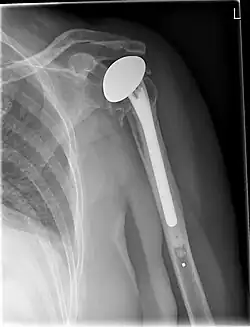

![]() X-ray of a shoulder prosthesis | |

Shoulder replacement is a surgical procedure in which all or part of the glenohumeral joint is replaced by a prosthetic implant. Such joint replacement surgery generally is conducted to relieve arthritis pain, improve joint mobility, and/or fix severe physical joint damage.[1]

Various materials can be used to make prostheses, however the majority consist of a metal ball that rotates within a polyethylene (plastic) socket. The metal ball takes the place of the patient's humeral head and is anchored via a stem, which is inserted down the shaft of the humerus. The plastic socket is placed over the patient's glenoid and is typically secured to the surrounding bone via cement.[13]